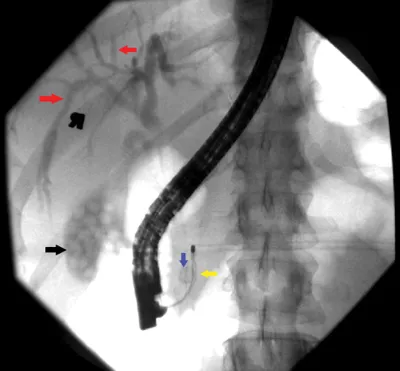

Figure 3.

Describe what you see and read on

This fluoroscopic image shows that the gallbladder (black arrow) and intrahepatic biliary ducts (red arrows) have been opacified with contrast. There is air in the common bile duct after biliary sphincterotomy, and a Dormia basket (yellow arrow) has engaged the stone (blue arrow) and is being used for its extraction.

A stone that was not seen on ultrasound was obstructing the common bile duct. This also explains why the patient had elevated LFTs, as the stone was causing biliary obstruction.